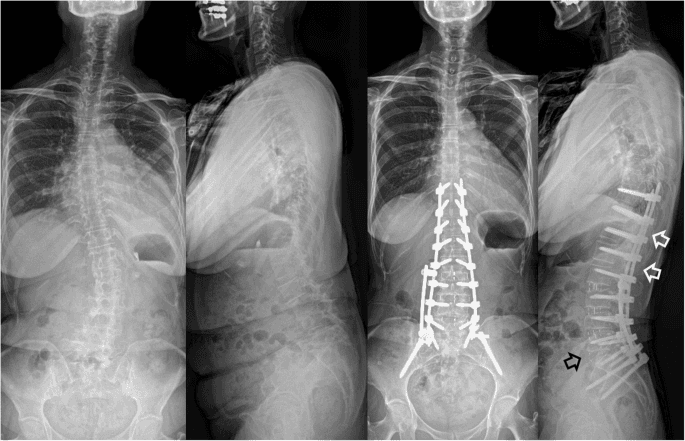

Scoliosis deformity correction with fusion is a surgical procedure for severe spinal curves, typically those greater than 45-50 degrees. The main goal is to straighten the spine and prevent the curve from worsening. This is achieved by 'fusing' together the affected vertebrae so they heal into a single, solid bone.

The surgeon makes an incision along the back to expose the curved portion of the spine. Screws, rods, and hooks are then attached to the vertebrae. The surgeon uses this instrumentation to carefully and safely correct the curvature. After the spine is realigned, a bone graft is placed between the vertebrae. Over several months, the vertebrae and the graft will fuse together, creating a permanent, rigid structure that holds the spine in the corrected position. This process eliminates motion in the fused segments, which stops the curve from progressing and can also alleviate pain.